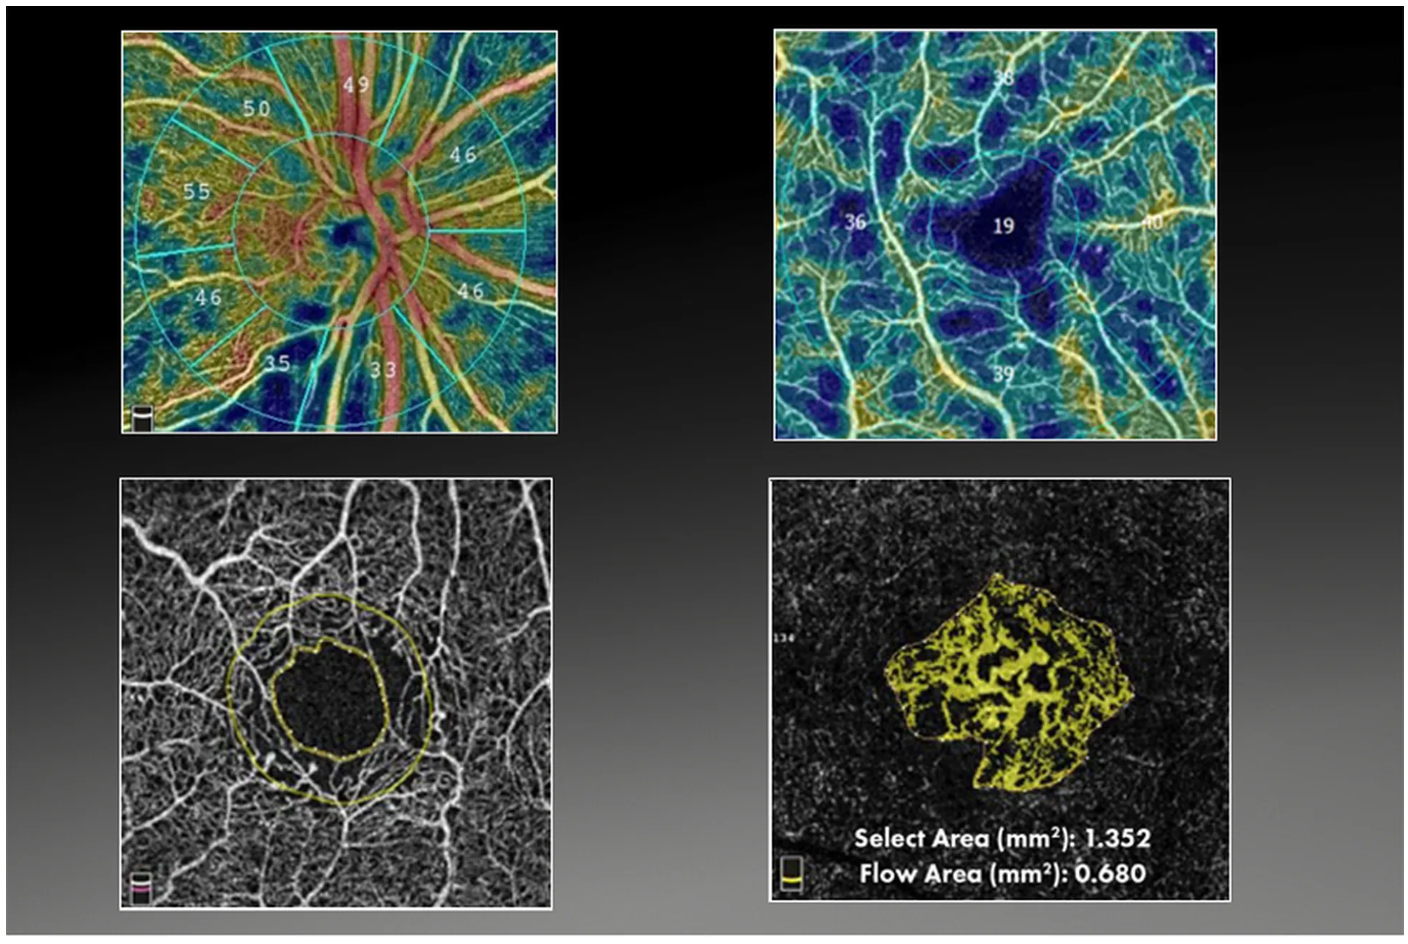

- Диапазон сканирования в режиме ангио-ОКТ — от 3х3 до 18х18 мм;

- Программа AngioAnaliticsTM для количественного анализа сосудов сетчатки;